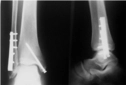

Bu yöntemler, kalça kırığının tam yerini ve türünü belirlemek için kritik öneme sahiptir. Tedavi YöntemleriKalça kırığının tedavisi, kırığın tipi, hastanın yaşı ve genel sağlık durumu gibi faktörlere bağlı olarak değişiklik gösterir. Genel olarak kullanılan tedavi yöntemleri şunlardır:

Tedavi süreci, hastanın yaşına ve genel sağlık durumuna göre özelleştirilmelidir. SonuçKalça kırığı, yaşlı bireyler için önemli bir sağlık sorunu oluşturmaktadır. Belirtilerinin hızlı bir şekilde tanınması ve uygun tedavi yöntemlerinin uygulanması, iyileşme sürecini hızlandırmaktadır. Bu nedenle, kalça bölgesinde herhangi bir yaralanma durumunda derhal tıbbi yardım alınmalıdır. Kalça kırıklarının önlenmesi için düşme risklerinin azaltılması ve uygun egzersiz programları uygulamak da büyük önem taşımaktadır. Ekstra BilgilerKalça kırıkları, genellikle osteoporoz gibi kemik erimesi hastalığı olan bireylerde daha sık görülmektedir. Bu nedenle, yaşlı bireylerin kemik sağlığını korumak amacıyla düzenli sağlık kontrolleri yaptırmaları, dengeli beslenmeleri ve yeterli miktarda kalsiyum ve D vitamini alması önerilmektedir. Ayrıca, düzenli egzersiz yapmak, kas gücünü artırarak düşme riskini azaltabilir. |